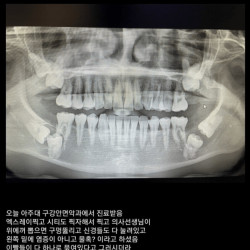

어떤 사랑니 사진.jpg

짤박스 | 05-13 21:03 | 조회: 1995